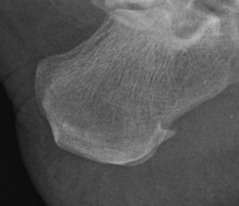

La quiropodogía es un tratamiento podológico, que aborda tanto problemas dermatológicos como alteraciones ungueales. Cuyo objetivo consiste en realizar una evaluación general para detectar cualquier anomalía en el pie, lo que permite prevenir que las lesiones se agraven (por ejemplo, diagnosticar un pie de atleta).

anomalías o infecciones de la lámina ungueal

verrugas plantares

pie diabético